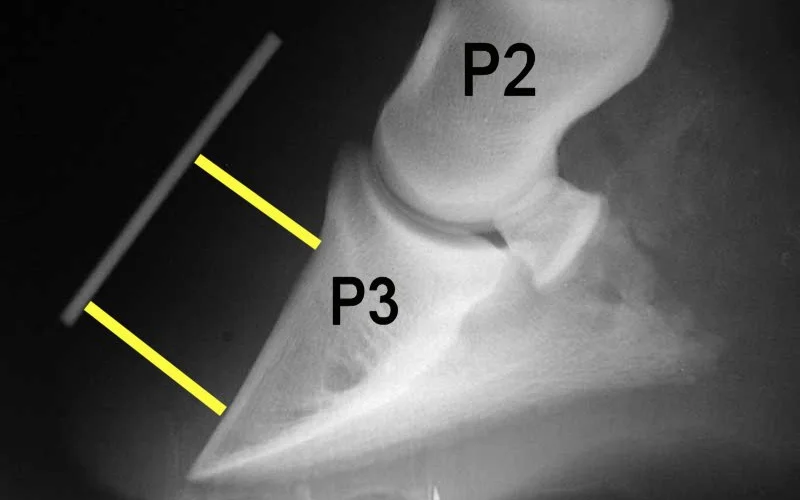

La laminitis es una de las afecciones más dolorosas y potencialmente incapacitantes que puede sufrir un caballo. Se trata de la inflamación de las laminillas sensitivas (tejido laminar), que son las estructuras que unen el hueso cofín (tercera falange o P3) a la pared interior del casco. Cuando estas laminillas se inflaman, el flujo sanguíneo se ve comprometido, lo que provoca un dolor intenso y, en los casos más graves, la desconexión o rotación de la tercera falange hacia la suela del casco.

El veterinario confirma el diagnóstico mediante exploración clínica y radiografías para medir el grado de rotación de P3 (se considera crítico a partir de 5,5°). El tratamiento urgente incluye: retirada inmediata del pasto, cama profunda de arena o viruta, crioterapia continuada (hielo en cascos durante las primeras 72 h), AINEs como fenilbutazona (2,2–4,4 mg/kg/día) y herrado ortopédico correctivo. El manejo a largo plazo requiere control estricto de la dieta (forraje con menos del 10 % de azúcares solubles), ejercicio gradual y revisiones radiológicas cada 3–6 meses.